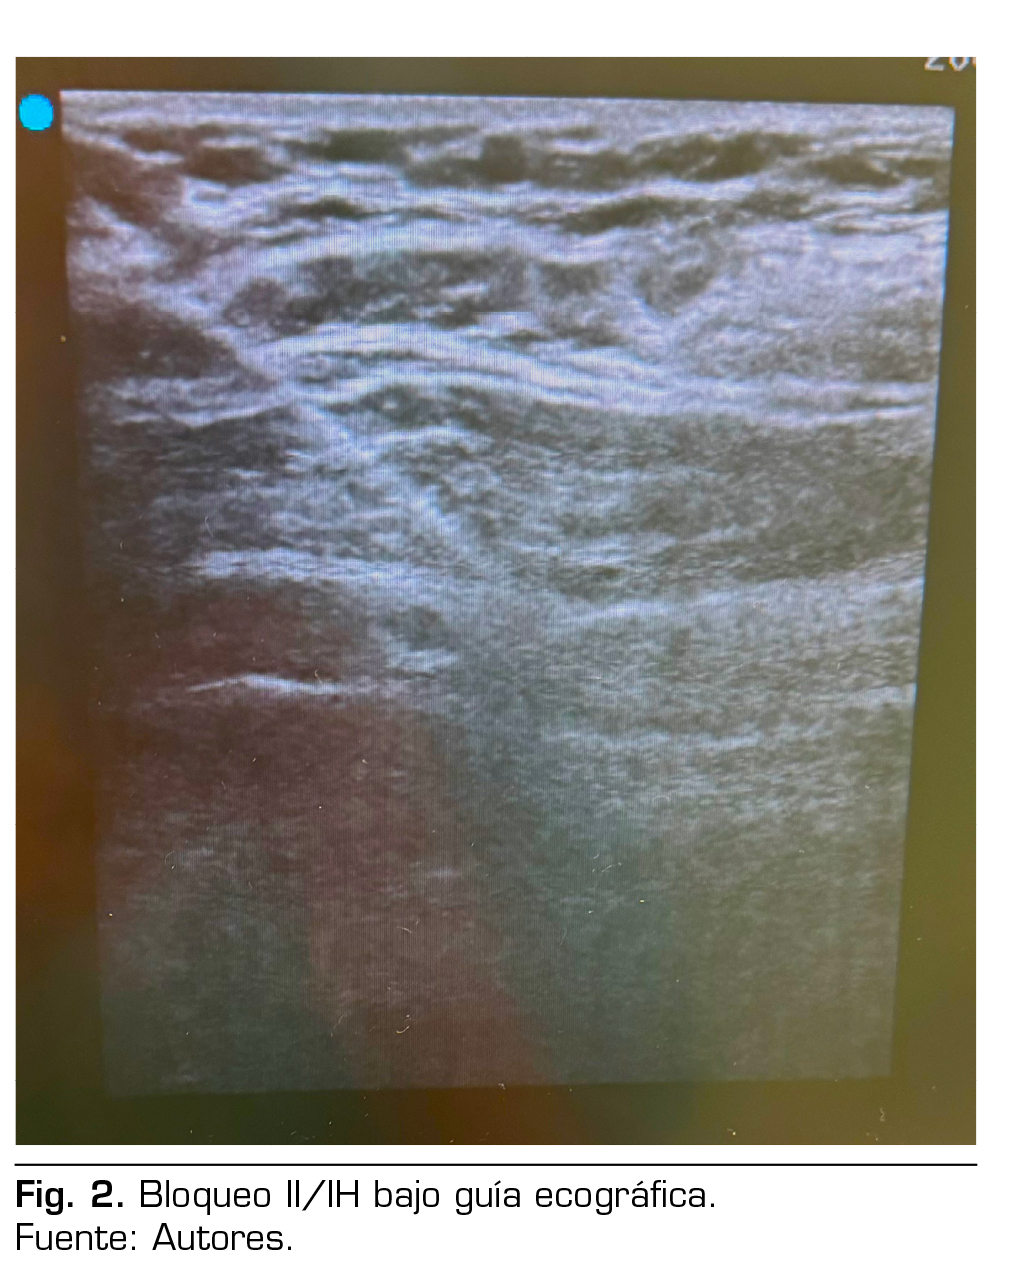

Presentación de caso: Presentamos el caso clínico de un paciente adulto mayor de 88 años ASA III, sometido a una hernioplastia inguinal electiva, bajo anestesia regional: bloqueo II/IH bajo guía ecográfica más sedación, manejo analgésico complementario con paracetamol y antinflamatorios, alta de cirugía médica ambulatoria a su domicilio y control postoperatorio sin complicaciones.

Case presentation: We present the clinical case of an 88-year-old adult patient ASA III, for elective inguinal hernioplasty, under regional anesthesia: Ilioinguinal-Iliohypogastric block under ultrasound guidance plus sedation, complementary analgesic management with paracetamol and anti-inflammatory drugs, discharge from outpatient surgery to his home and postoperative control without complications.

Figura 1